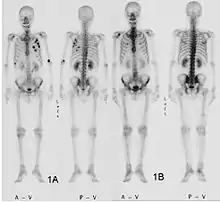

- Vues de fractures pathologiques

Scintigraphie corps entier avec 99mTc-HDP de la patiente avec une fracture du bras due à une métastase du cancer du sein

Scintigraphie osseuse

La scintigraphie osseuse est actuellement encore le meilleur moyen de diagnostic des métastases osseuses. Ce procédé est relativement sophistiqué, coûteux et soumis à quelques limites diagnostiques[90]. Contrairement à la radio, on peut avec la scintigraphie représenter assez simplement l'ensemble des attaques du squelette[87]. Une scintigraphie osseuse est normalement bien plus sensible pour la détection des métastases osseuses qu'une radio. La sensibilité de la scintigraphie osseuse est assez élevée, avec 95 %. En moyenne, avec cette méthode, les métastases osseuses sont détectées six mois avant leur mise en évidence sur la radio[113]. Par contre la spécificité est substantiellement plus faible[114], car presque toutes les modifications tumorales ou inflammatoires du squelette conduisent à un enrichissement en radiotraceurs dans le voisinage. Le remodelage plus élevé et les processus de réparation dans la bordure des métastases osseuses ostéolytiques conduisent à une accumulation plus élevée du radiotraceur, visible comme un « point chaud » sur l'image de scintigraphie[115]. Un phénomène observable de rebond (flare up) peut être dû à l’augmentation de l’activité ostéoblastique au niveau des zones d’ostéolyse tumorale clinique, dont la colonisation métastatique a été éradiquée par le traitement ; il ne doit pas être confondu avec une progression métastatique, au risque de modifier le traitement de façon intempestive[116]. Dans les métastases osseuses de cancer du poumon ou du sein, la néoformation réactive d'os peut dans de rares cas être absente[117]. Sur la scintigraphie, ceci apparaît alors comme un « point froid », un domaine avec une absorption réduite du radiotraceur[118].

La scintigraphie osseuse est avant tout utilisée pour le contrôle de la thérapie, que ce soit une chimiothérapie, une radiothérapie externe ou métabolique, pour la détermination des stades, notamment pour les cancers avec tumeur primitive inconnue, et pour le suivi après cancer[87].